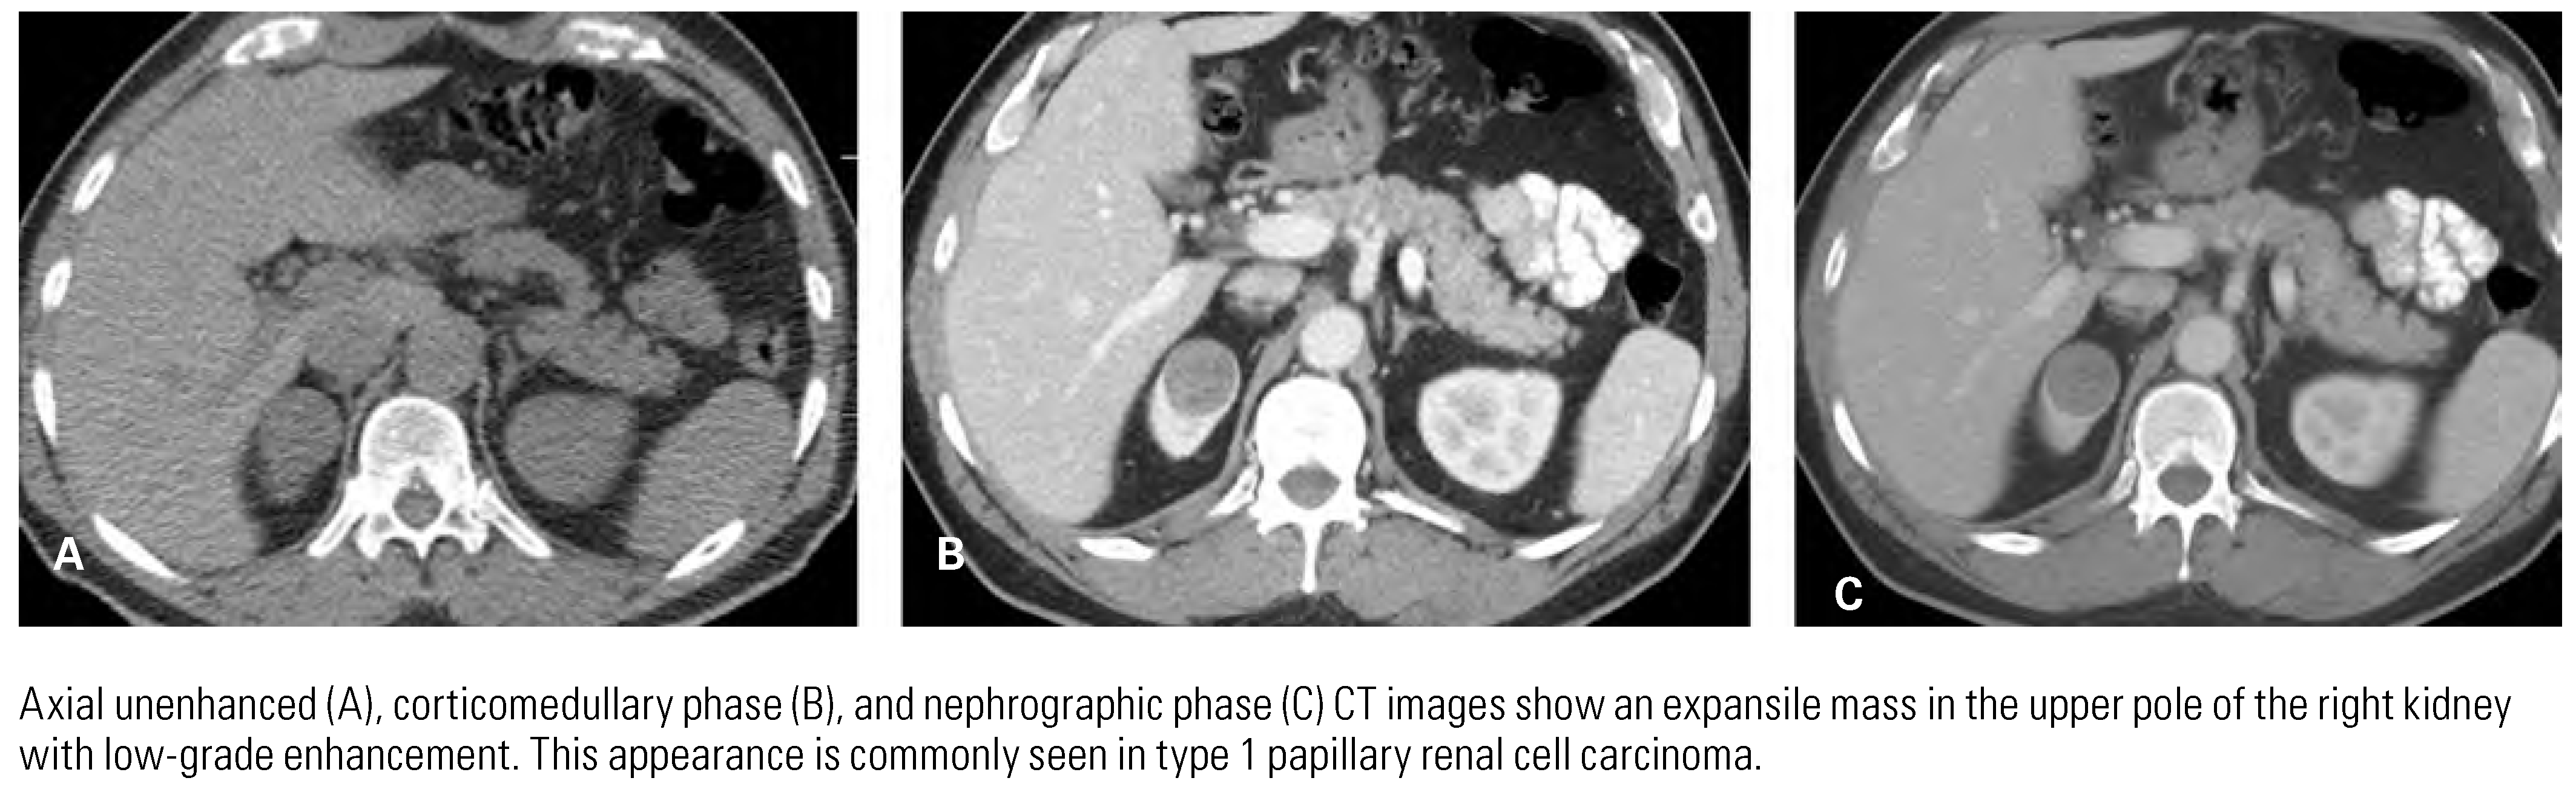

Papillary Renal Cell Carcinoma